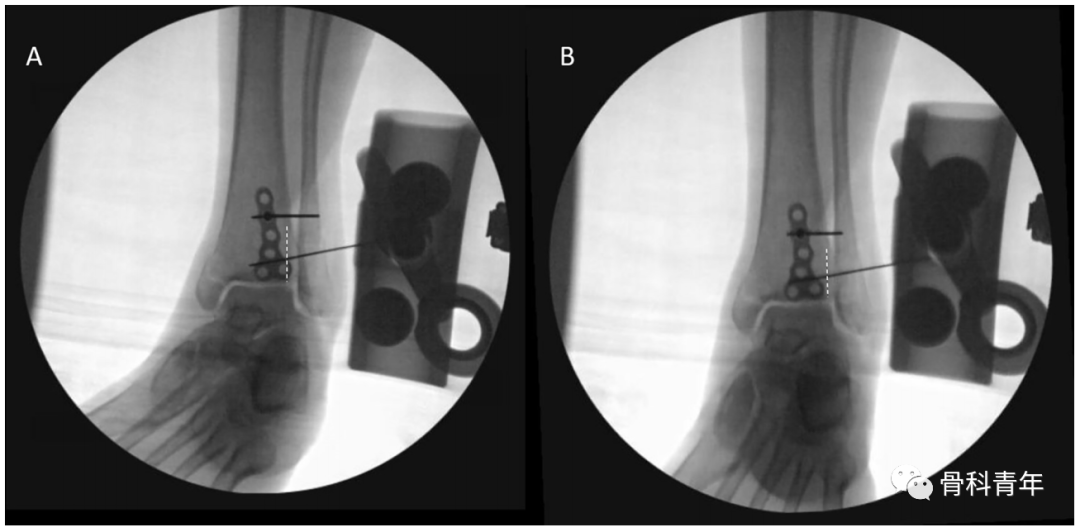

依上述研究结果,在如下的后踝钢板固定中,透视钢板部分位于PVSL线外侧,有影响下胫腓风险,因此将钢板内移至PVSL线内。

▲ 图中白色虚线即为PVSL线。